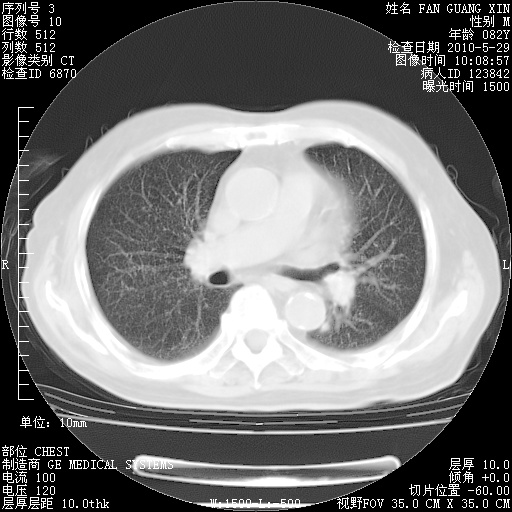

再治疗10天后的肺部CT

阅读此次胸部CT,肺间质渗出性改变较入院时有吸收。目前从体温、白细胞、中性分叶明显增高,肯定存在细菌感染(发生医院感染哦,若无消化道及泌尿系统等感染的依据,肺部感染可能大)。若你院头孢哌酮舒巴坦钠耐药率较高,同意你的方案,若48小时体温仍高,可考虑使用碳青霉稀类抗菌药物,同时可予超声雾化、注意滴数时加大液体量。白蛋白33.30g/L较低哦,需加强营养等支持治疗。